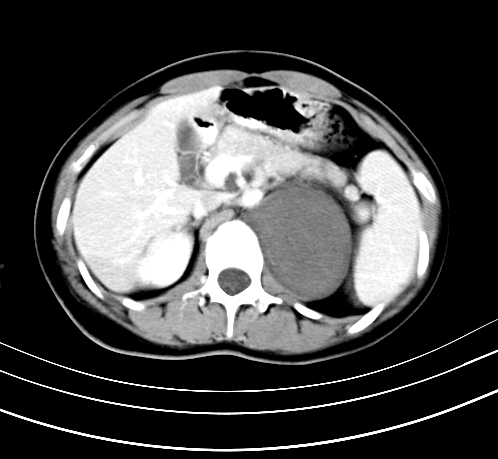

动脉期